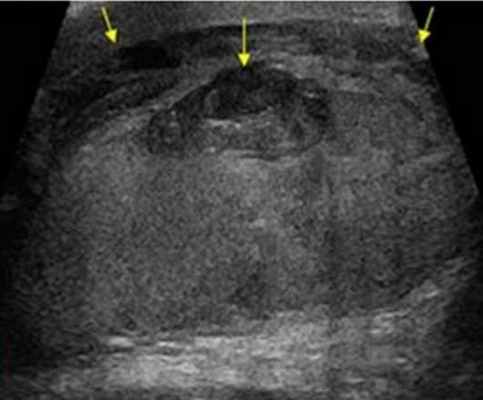

УЗИ после травмы мошонки: гематоцеле по краям, кровоизлияние в тело яичка в центре

Диагностика

Основным методом диагностики является УЗИ мошонки. При необходимости его выполняют с допплерографией, чтобы проверить кровоснабжение новообразования. В ряде случаев достаточно диафаноскопии. В ходе этой процедуры мошонку просвечивают лучом яркого света. По степени его прохождения через опухоль судят о ее содержимом. Таким образом можно отличить кисту от грыжи.